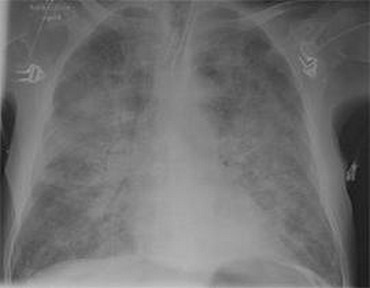

Pre-intubation CXR for the case found here:

(CXR source: https://www.med-ed.virginia.edu/courses/rad/cxr/pathology2Bchest.html)